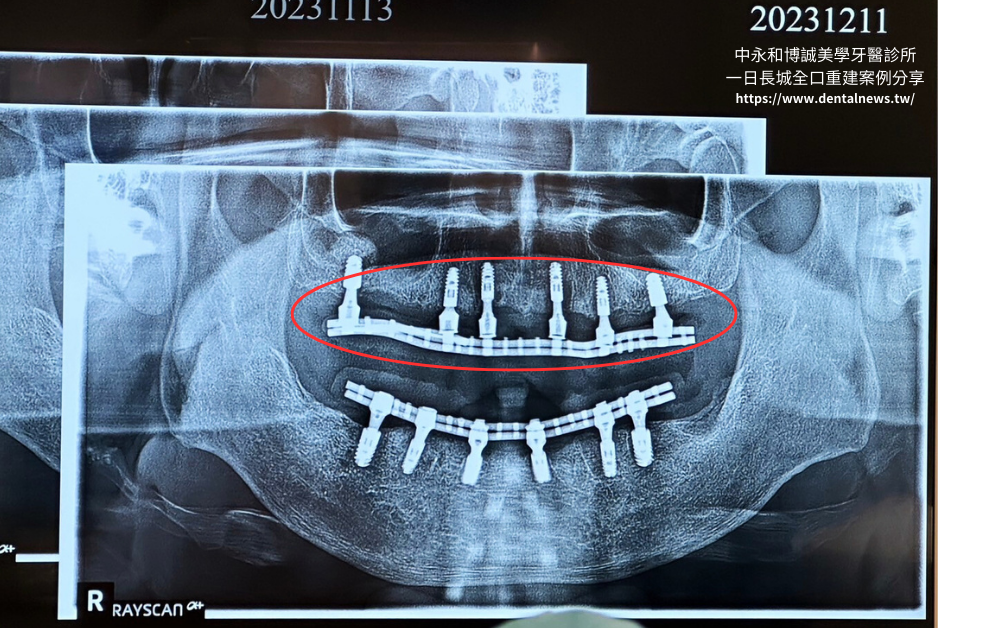

「一日長城全口重建植牙」厲害的地方在於能夠地將4~6個植體牢牢固定於齒槽骨中,植體可以互相提升整體的穩固感和穩定性,同時也確保植牙更能輕鬆應對咀嚼和其他口腔運動所帶來的各種壓力,植牙變得如此簡單,不再是煩惱!

一日長城的優點在於使用4~6根較短的植體,植入齒槽骨中,能夠提供較高安全性。在假牙支撐方面,一日長城使用鈦金屬銲接骨架,並提供客製化假牙製作服務,讓患者在咀嚼的時候能夠達到與真牙無異的效果。

透過巧妙的「磨擦穩固」設計,目的是在日後的維修和治療上都更加方便,但也實現讓假牙固定穩如泰山的目標,不僅不容易脫落,想自行拔開都相當困難。